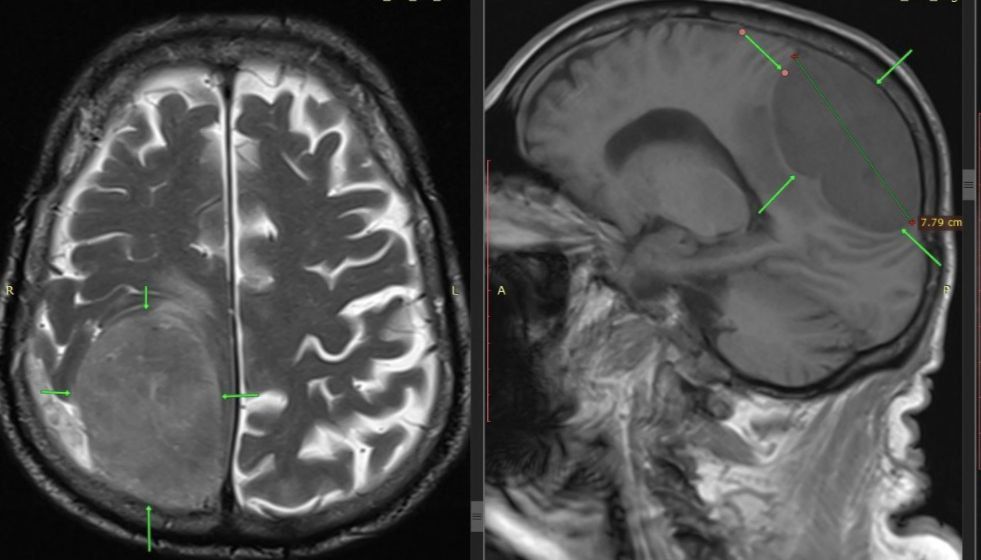

• В Пятигорске мужчине удалили опухоль мозга размером с лимон

В Пятигорске специалисты городской клинической больницы удалили из головы 85-летнего мужчины опухоль размером с лимон. Об этом сообщается в телеграм-канале медучреждения.

Когда пенсионера доставили в больницу, у него уже отказала левая половина тела. Врачи заподозрили инсульт. Обследование показало опухоль размером 87 см в правой части мозга.

Потребовалась ювелирная работа команды врачей. Дело в том, что удаление такого крупного новообразования вызывает резкие скачки внутричерепного давления, это влияет на работу сердца.

Операция прошла успешно: медики выполнили костно-пластическую трепанацию черепа и удалили опухоль. Пациент быстро пошел на поправку, движения в левой половине тела восстановились.

Фото: ГКБ Пятигорска